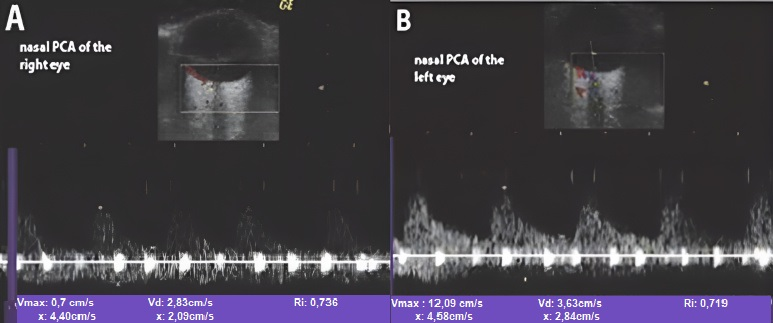

- In the acute phase of unilateral clinical eye involvement, absent (undetectable) signals in the homolateral PCAs (not corresponding to homolateral internal carotid artery occlusive disease) are classified as Doppler US features in acute arteritic AION (consecutive to GCA). In addition, we can identify a high resistance index (RI), with decreased velocities (especially EDV) in all retrobulbar vessels, in both orbits [9,10,11,12,13,14,15,60,61,62] (Table 2) [13].

- GCA acute cases with no evident clinical ocular involvement present a decrease in arterial flow in bilateral orbits, with increased RI, and diminished velocities (especially EDV). The severely diminished flow in the PCA, associated with diminished flow in the CRA and very high flow in the OA (all on the affected side) are the common US features in this type of patient. This US aspect is an essential predictor of an imminent A-AION and needs prompt treatment with high-dose corticosteroids [9,10,11,12,13,14,15,60,61,62] (Figure 7) [11].